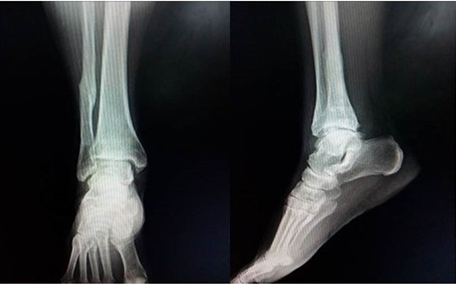

A las 12 semanas se retiró el aparato tras constatarse la consolidación de la fractura peroneal, en este momento comienza la marcha con apoyo. La recuperación total de la paciente se logró a los cinco meses de la cirugía.

Teniendo en cuenta que la fijación externa no es un método de tratamiento habitualmente empleado en la resolución de estos casos se realizó un seguimiento por cinco años de la paciente operada, durante este tiempo se pudo constatar la buena función articular, la no presencia de edema residual así como la poca degeneración articular existente teniendo en cuenta la gravedad de la lesión inicial. (Fig. 5 y 6).